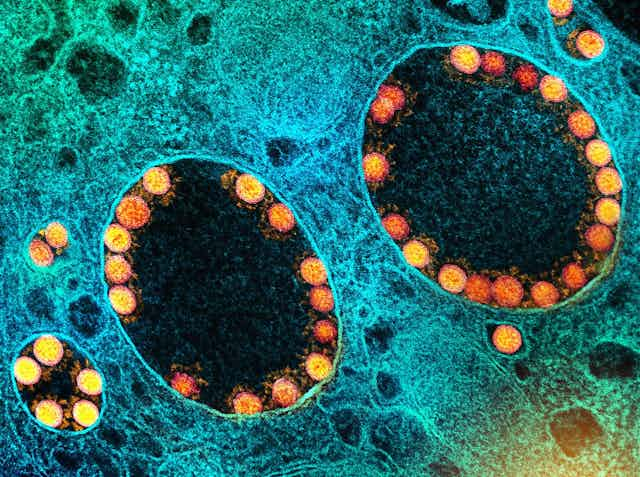

Desde la descripción del primer virus del tabaco por el científico Dmitri Ivanovsky en 1892, se han descrito más de 9 000 especies de virus en detalle, aunque se estima que hay millones de tipos en el ambiente. Y todos son extremadamente simples. Están formados por material genético (ARN o ADN), una cápsida proteica y, en algunos casos, también una cubierta de lípidos.